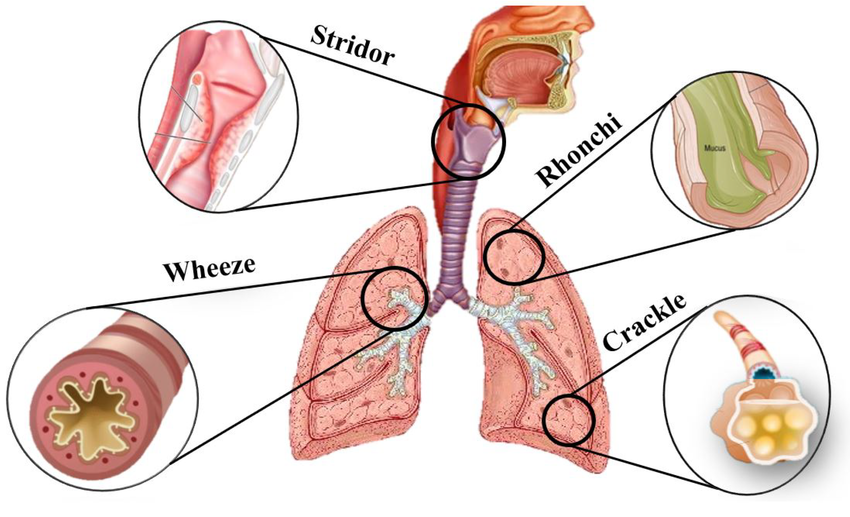

Wheezing sound (વ્હીઝીંગ સાઉન્ડ):

- વ્હીઝ એ હાઇ પીચ (High-Pitch) મ્યુઝિકલ સાઉન્ડ છે.Wheezing sound ત્યારે થાય છે જ્યારે એરવે (Airway) – એટલે કે breathing passage – Narrowed અથવા Partially Obstructed થઈ જાય છે. વ્હીઝ સાઉન્ડ એ એક્સપીરેશન (શ્વાસ છોડતી વખતે) દરમિયાન જ સંભળાય છે.

Stridor (સ્ટાઇડર):

- સ્ટ્રાઇડર (Stridor) એ એક અબનોર્મલ હાઈ-પિચ્ડ (High-pitched) બ્રીધીન્ગ સાઉન્ડ છે, જે સામાન્ય રીતે ઇન્સ્પિરેશન (Inspiration) દરમિયાન સાંભળાય છે.

આ અવાજ એ સમયે બને છે જ્યારે અપર એરવે (Upper Airway) – ખાસ કરીને લેરિંક્સ (Larynx) અથવા ટ્રેકિયા (Trachea) – નેરો (Narrowed)થઈ જાય છે અથવા ઓબ્સ્ટ્રક્ટેડ (Obstructed) થાય છે. - એટલે કે, Stridor = Inspiratory high-pitched harsh sound due to upper airway obstruction.

Rhonchi (રહોન્કાય) :

- રહોન્કાય (Rhonchi) એ એક અબનોર્મલ કન્ટિન્યુઅસ બ્રેથ સાઉન્ડ (Abnormal Continuous Breath Sound) છે, જે સામાન્ય રીતે લો-પિચ્ડ (Low-pitched) અને સ્નોરીન્ગ/ ગર્ગલીન્ગ (Snoring / Gurgling) જેવા અવાજ તરીકે સંભળાય છે.

- આ અવાજ મોટાભાગે એરવે (Airway) માં મ્યુકસ (Mucus) અથવા અન્ય સિક્રેશન (Secretions) ભરાય જવાથી બને છે, ખાસ કરીને મોટા બ્રોન્કી (Large Bronchi) માં. જે સામાન્ય રીતે Expiration (શ્વાસ છોડતી વખતે) સંભળાય છે, ક્યારેક Inspiration દરમ્યાન પણ.

Fine crackles (ફાઇન ક્રેકલ્સ):

- ફાઇન ક્રેકલ્સ (Fine Crackles) એ એક પ્રકારનો અબનોર્મલ ડિસ્કન્ટિન્યુઅસ (Discontinuous) બ્રેથ સાઉન્ડ છે, જે Short, Soft, High-pitched Popping or Crackling જેવા અવાજ રૂપે સાંભળાય છે.

- આ અવાજ સામાન્ય રીતે Inspiration (શ્વાસ લેતી વખતે) દરમ્યાન સાંભળાય છે, ખાસ કરીને Lungsના બેઝ (Bases) પર.

તે દર્શાવે છે કે lungsના નાના એરવે અથવા એલ્વિઓલાઈ (Alveoli) માં પ્રવાહી (Fluid) અથવા કોલેપ્સ થયેલા એર સ્પેસ (Collapsed Air Spaces) ખુલતાં હોય છે.